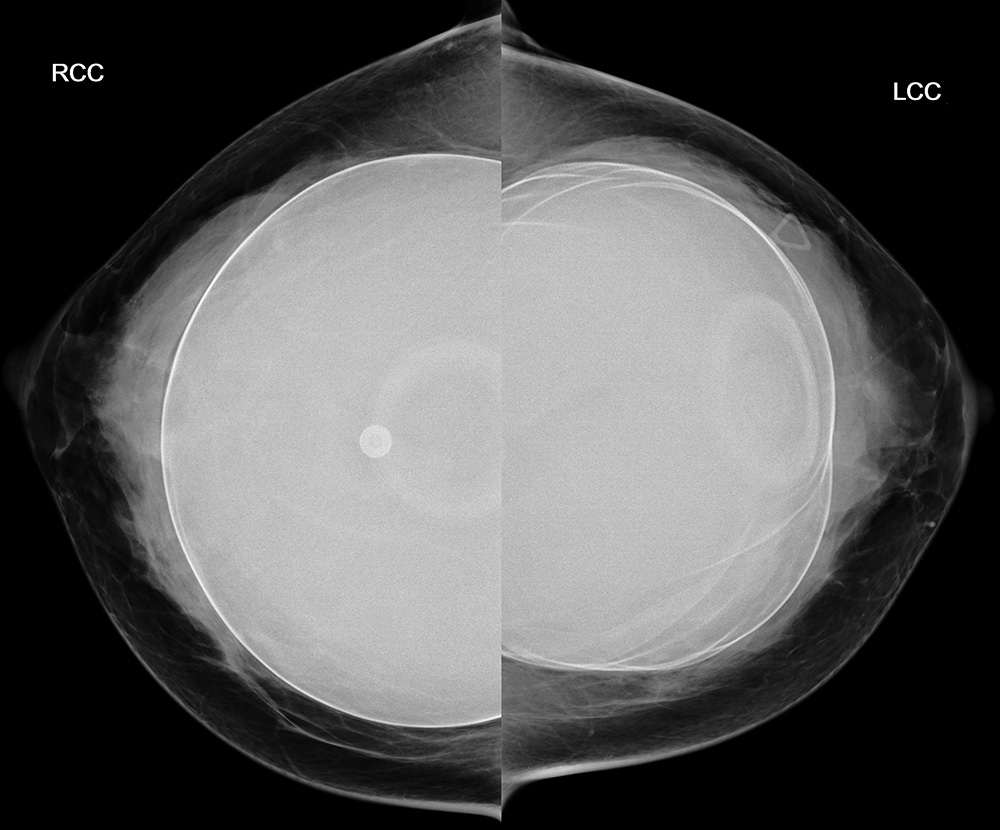

◂Breast Anatomy